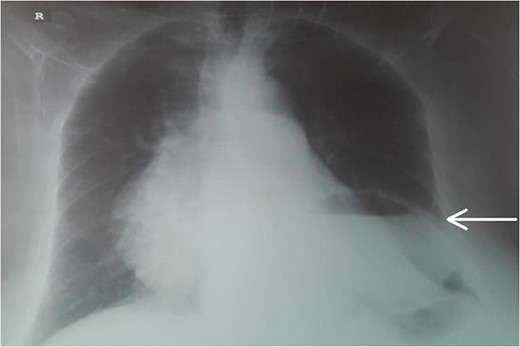

An 87-year-female patient was admitted to emergency department complaining about vomiting for the past 7 days with mild abdominal pain. The patient was hemodynamically stable, had sluggish bowel sounds and soft abdominal wall with mild tenderness. The patient also suffered from atrial fibrillation, heart failure, myelodysplastic syndrome, hiatus hernia and cholelithiasis. The findings of the laboratory tests were unremarkable. Plain chest and abdominal radiograms revealed hiatus hernia with gastric dilation (Fig. 1), a few air-fluid levels and pneumobilia, with delineation of extrahepatic and intrahepatic bile ducts by air (Fig. 2). A nasogastric tube was inserted, which drained biliary content. An abdominal computed tomography (CT) scan revealed the presence of air in the intrahepatic bile ducts, free air and leakage of oral contrast agent in the hepatic hilum and subhepatic space and an impacted gallstone in the third portion of the duodenum (Figs 3 and 4). The diagnosis of cholecystoenteric fistula and proximal gallstone ileus was set.

Abdominal CT scan (coronal plane). The long arrow shows the impacted gallstone and the short arrow shows the free air and the leakage of oral contrast agent.